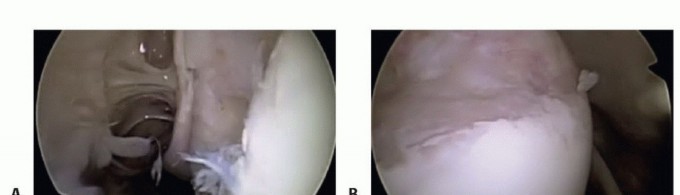

There is an old orthopedic adage: "If it doesn't bleed, it doesn't heal." The fundamental error in novice Bankart repairs is inadequate tissue mobilization. The labrum and capsule are often scarred medially down the glenoid neck, a classic ALPSA variant. Using an arthroscopic elevator, rasp, or radiofrequency ablation wand, the capsulolabral complex must be aggressively elevated off the anterior glenoid neck.

Image

This release must extend inferiorly past the 6 o'clock position (often requiring a switch of the viewing portal to the anterosuperior portal for adequate visualization) and medially until the red muscle belly of the subscapularis is clearly visualized. The tissue must "float" freely, allowing it to be shifted superiorly and laterally onto the glenoid face without any resting tension.

Once mobilized, the anterior glenoid rim is meticulously decorticated using a motorized burr or aggressive rasp. The goal is to remove the eburnated, sclerotic bone and create a bleeding, cancellous bone bed. This optimizes the biological healing environment, allowing the shifted capsulolabral complex to integrate solidly with the osseous glenoid.